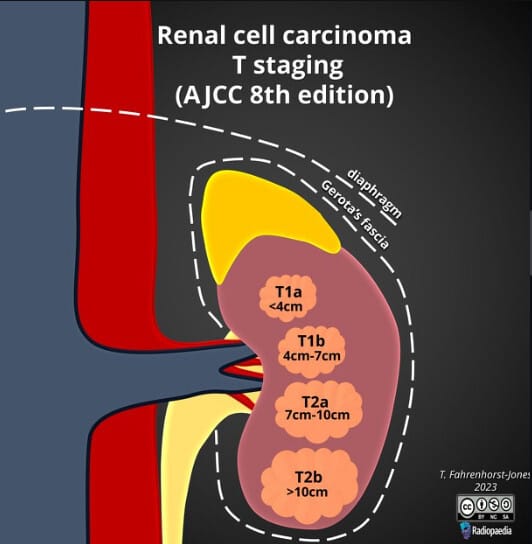

Renal cell carcinoma 병기

신세포암(Renal cell carcinoma, RCC)의 병기는 종양의 크기와 신장을 넘는 침범 정도, 림프절 전이 여부, 원격 전이 여부에 따라 TNM Staging 체계로 분류합니다. 병기는 예후 예측과 치료 결정에 매우 중요합니다.

Fahrenhorst-Jones T, Renal cell carcinoma T staging (AJCC 8th edition). Case study, Radiopaedia.org (Accessed on 07 May 2025) https://doi.org/10.53347/rID-177572

| Stage I (T1N0M0) |

| 종양의 크기가 7cm 이하이며 신장 내에 국한됨. 림프절 전이와 원격 전이는 없음. |

| Stage II (T2N0M0) |

| 종양 크기가 7cm를 초과하나 여전히 신장 내에 국한됨. 림프절 전이와 원격 전이는 없음. |